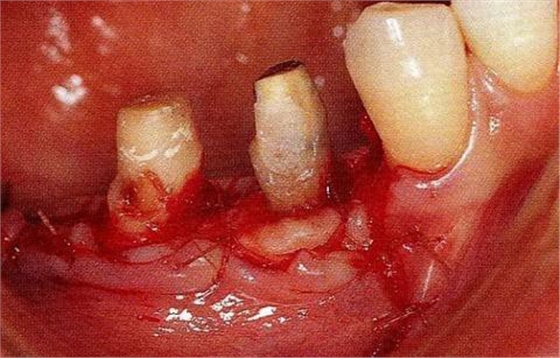

圖17-3▲拔牙的同時(shí)做骨外科處理,讓殘留的骨可以盡量平坦化。為了獲得頰側(cè)的附著齦,采用了游離齦瓣的處理。